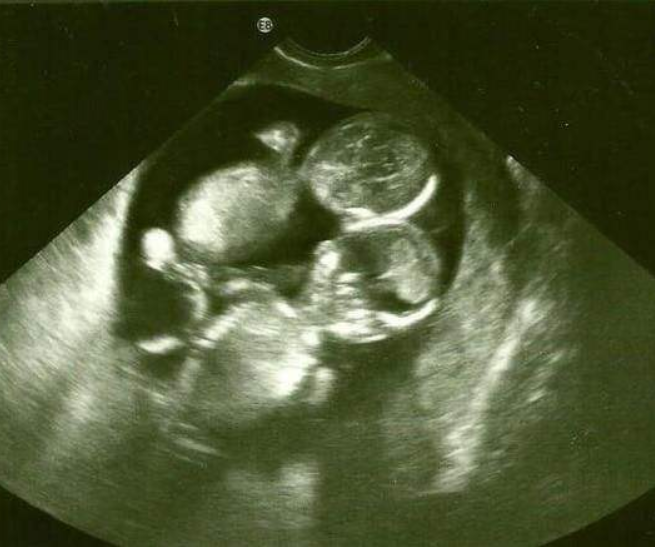

一般而言,女性每月會產生一個卵子,而男性會產生無數個精子,這些精子經過層層的考驗,最后只有一個精子能夠順利地和子宮內的卵子結合,形成孕育生命的受精卵,所以大多數人懷有的是單胎。但是如果女性在一個排卵周期內排出兩顆卵子,由兩個卵子分別受精形成的兩個受精卵,以后分別發育成兩個胎兒。

第二,兩個胎心,兩個胎動

懷雙胞胎從在娘胎肚子里就開始費錢了,做B超和胎心監測都要雙份錢。想想米媽做胎心監測的時候,一顆碩大的肚子上綁著兩個聽胎心的機器也是很特別啊。數胎動對雙胞胎媽媽來說不是件易事,兩個寶寶還喜歡做反向運動,左數一下,右數一下,沒一會兒就忘了該數誰的胎動次數了。